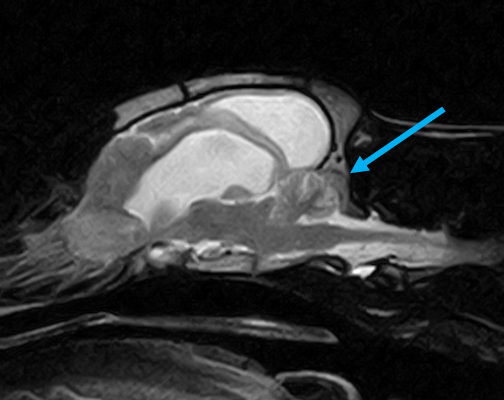

W obrębie mózgowia i trzewioczaszki najczęstszymi wskazaniami do badania MRI są:

• wstępna diagnoza gruczołu przysadki

• ocena patologii ucha zewnętrznego, środkowego oraz wewnętrznego

• patologie w obrębie oczodołów i struktur przyległych – ocena zmian pourazowych, zapalnych i nowotworowych

• zmiany zaoczodołowe i około zębowe – diagnostyka przewlekłych infekcji